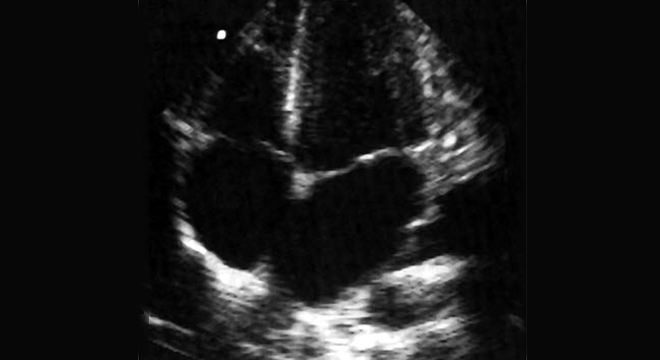

Herzinsuffizienz: Echokardiographie (Herzultraschall)

• Herz-Ultraschall (Echokardiographie )